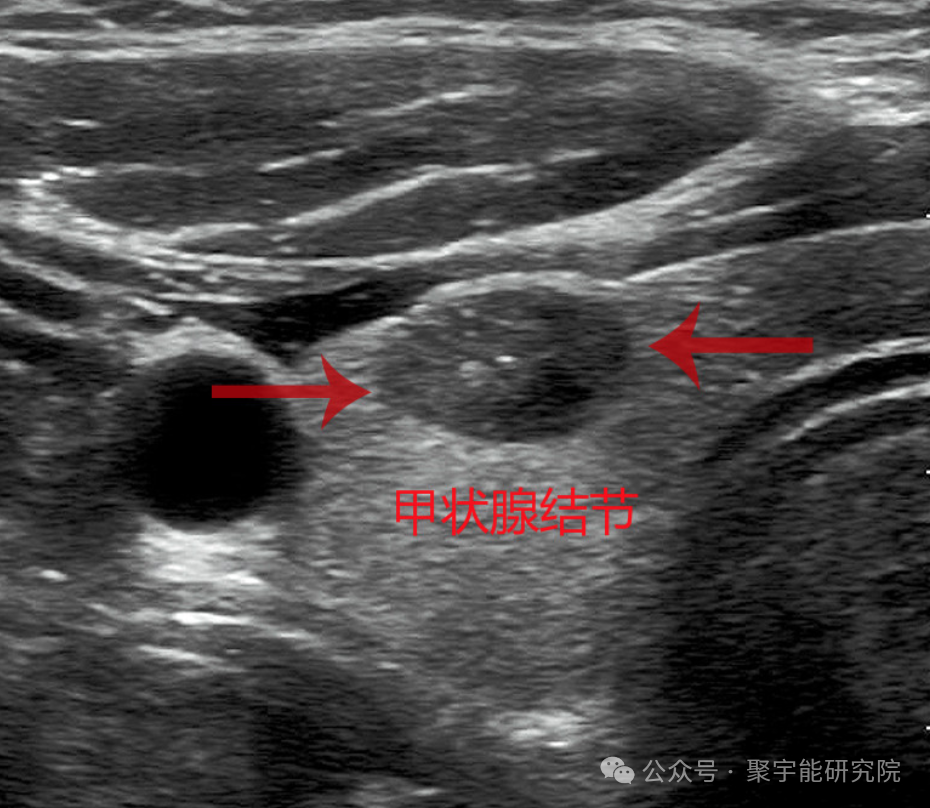

我和动力液的故事 | 小心颈部“炸弹”—甲状腺结节

甲状腺结节在各个年龄的人群中均可见到。在成人群体中,以体检方式统计的发病率为5%~7%,以超声检查方式统计的发病率为20%~76%(该结果监测的人群相同)。女性多于男性,男女之比约1:3.83。